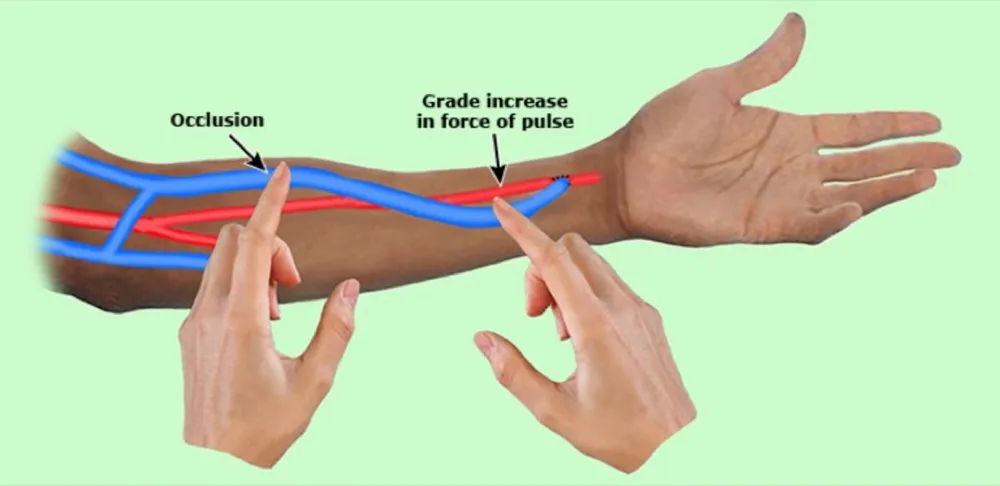

Exame e oclusão transitória do acesso AV

A presença de uma FAV grande e distendida ou de um enxerto AV com aumento de pulso muito forte sugere fluxo sanguíneo elevado e deve levar a uma avaliação para determinar o efeito do acesso na hemodinâmica sistêmica. Quando a FAV é ocluída transitoriamente (30 segundos), o grau de aumento (aumento) do pulso

arterial distal à anastomose AV é proporcional ao fluxo arterial.

A oclusão máxima transitória (esfigmomanômetro insuflado a 50 mmHg acima da pressão sistólica por 30 segundos) de um acesso geralmente diminui a frequência cardíaca, aumenta a pressão arterial e reduz a pressão

venosa; isso foi denominado sinal de Nicoladoni-Branham. Deve ser realizado por profissional experiente e confesso que nunca fiz na prática (comenta depois se você já viu ou já fez essa técnica😊)

Foi demonstrado que o sinal de Nicoladoni-Branham está relacionado à ativação dos barorreceptores arteriais e ao aumento da sensibilidade do barorreflexo arterial.

Além da diminuição da frequência cardíaca, há também aumento da pressão arterial e uma diminuição do débito cardíaco. Em uma revisão de 17 pacientes, aumentos na resistência vascular sistêmica e na pressão arterial média durante a oclusão pneumática de uma fístula AV cirúrgica foram preditivos de uma redução na hipertrofia ventricular esquerda (HVE) após a ligadura da fístula AV.